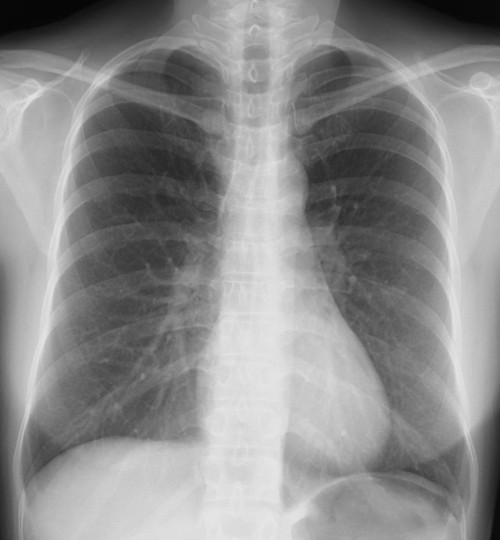

何処に異常陰影があるでしょうか?

肩甲骨に重なって見逃しやすいが、仮骨形成が始まった右第7肋骨骨折を診断できる。

右第4肋骨と胸椎の肋骨頭関節に関節面に一致して陰影をみとめる。

左鎖骨、胸鎖関節に近接した約1.5cmの円形陰影があり、辺縁は不規則(毛羽立ってみえる)になっている。陰影は大動脈・縦隔とのシルエットサインはみられず左肺S1+2に存在すると考えられ、肺門部のリンパ節腫脹はみられない。

縦隔陰影の拡大、大動脈の拡張をみとめる。右肺門肺動脈に重なって半球様の陰影(径2.7cm)が確認できる。肺門のリンパ節腫大等はない。

[評価]S6の炎症性偽腫瘍、結核、肺がん等の可能性がありCT等の検索・喀痰細胞診・生検が必要になる。